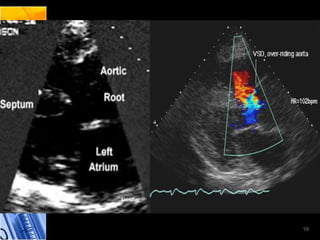

Ecocardiograma modo M

• Cabalgamiento aórtico y HVD

• Contraste  Cortocircuito Venoarterial

Ecocardiograma bidimensional

• Gran defecto septal interventricular y cabalgamiento

aórtico

Fonomecanocardiograma • Soplode la estenosis pulmonar y reconoce IIp retrasado • Prueba de nitrito de amilo demuestra un comportamiento paradójico del soplo expulsivo Ecocardiograma modo M • Cabalgamiento aórtico y HVD • Contraste  Cortocircuito Venoarterial Ecocardiograma bidimensional • Gran defecto septal interventricular y cabalgamiento aórtico Laboratorios • Policitemia secundaria 18